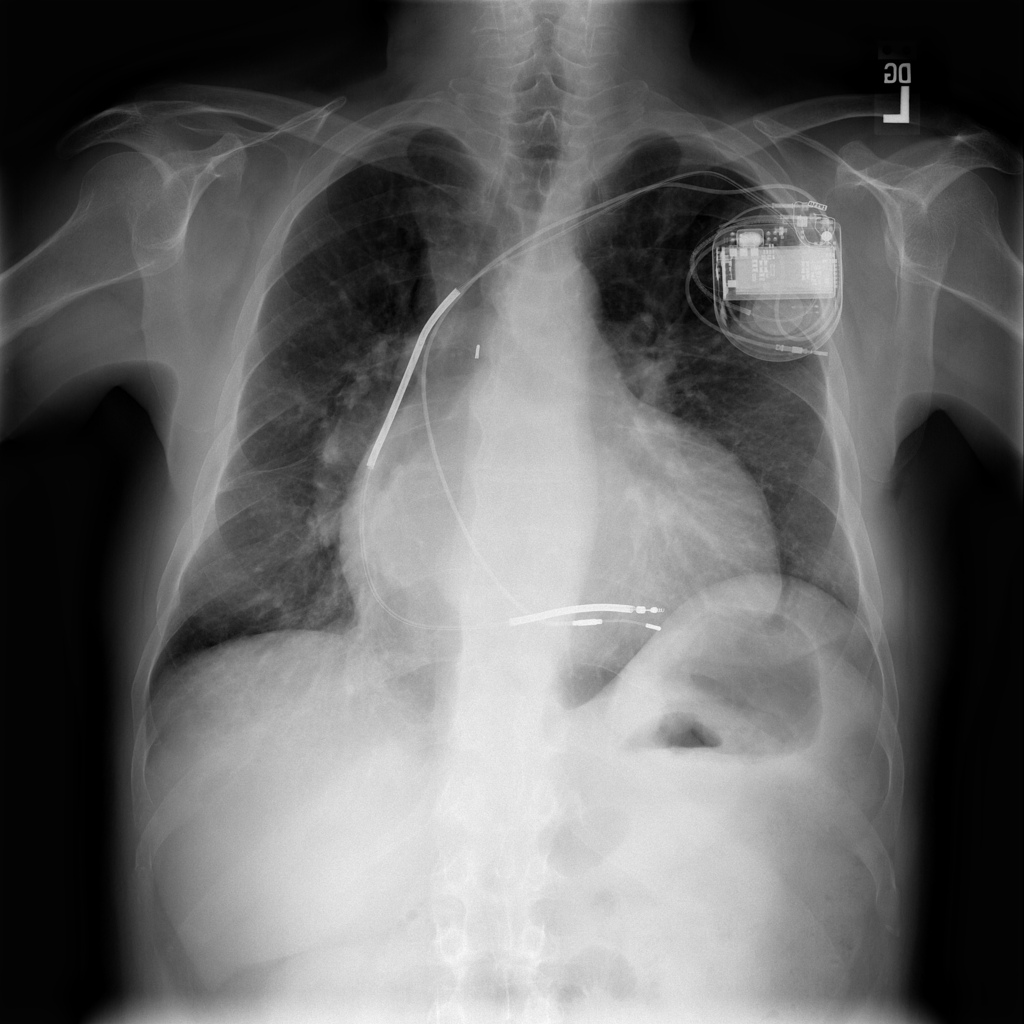

PAT-AE5C · IMG-000Cardiomegaly

PAT-AE5C · IMG-000

PA